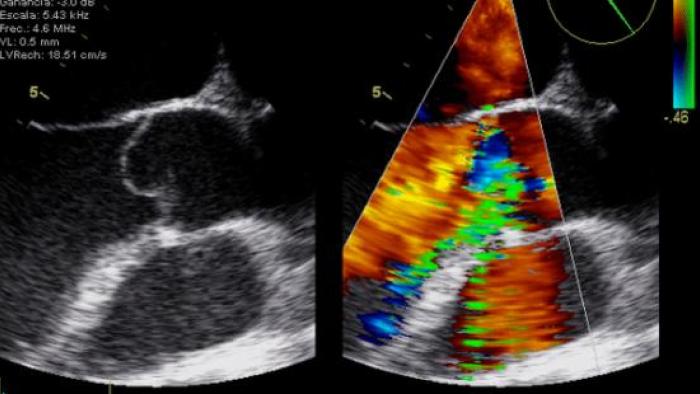

Noticias Todas las noticias y la información de última hora sobre la asistencia, la investigación, la docencia y la gestión que hacemos en Vall d'Hebron Barcelona Hospital Campus. ¡No te pierdas ningún detalle! Año202520242023 MesJanuaryFebruaryMarchAprilMayoJuneJulyAugustSeptemberOctoberNovemberDecember Fulltext search Buscar Evobrutinib reduce rápidamente las lesiones cerebrales en la esclerosis múltiple recurrente 09/05/2019 El Robot Pol abre las puertas del Museu del Barça a nuestros pacientes más pequeños 09/05/2019 Un estudio confirma que las mujeres tienen más riesgo que los hombres de morir cuando sufren un ataque al corazón 08/05/2019 El Dr. Rafael Esteban Mur recibe el galardón Medicina Siglo XXI en la categoría de Hepatología 07/05/2019 Vall d’Hebron celebra la jornada Hablando claro sobre el Cáncer de Ovario 07/05/2019 Nos sumamos al proyecto PortAventura Dreams village para mejorar la calidad de vida de los pacientes pediátricos 06/05/2019 Acogemos la exposición “Pompeu Fabra. Una lengua completa” 02/05/2019 Ganamos el prestigioso VBHC Dragons’ Grant & Endorsement dentro del proyecto europeo PED 29/04/2019 Comunicado sobre la muerte de dos prematuros extremos en Vall d’Hebron 28/04/2019 El Hospital de Día de Neurorrehabilitación celebra 10 años como referente en el tratamiento de los pacientes con lesiones cerebrales 28/04/2019 Profesionales de Vall d’Hebron organizan un curso de cirugía en el marco del Congreso Mundial de Histeroscopia 25/04/2019 ¿Pueden las partículas diésel causar asma en personas sanas? 24/04/2019 Éxito del curso de ecocardiografía básica para no cardiólogos 23/04/2019 Nuestros pacientes reciben las #RosesAmbCor dedicadas por los pasajeros de Ferrocarrils 22/04/2019 Acogemos por primera vez el Curso de Epilepsia para Residentes de Neurología de la SEN 16/04/2019 El Curso de Patología Endocrina Médico-Quirúrgica llega a la 25ª edición 16/04/2019 Celebramos la Diada de Sant Jordi con nuestros pacientes 16/04/2019 Vall d'Hebron impulsa el primer registro completo de pacientes con sarcoma del Estado 14/04/2019 Curso de Actualización en Enfermedad Celíaca 11/04/2019 La Mona de Pascua más famosa de Cataluña sale por primera vez de la pastelería Escribà y se presenta en Vall d'Hebron 11/04/2019 Paginación « Primera Primera página ‹ Anterior Página anterior … 83 84 85 86 87 88 89 90 91 … Siguiente › Siguiente página Última » Última página